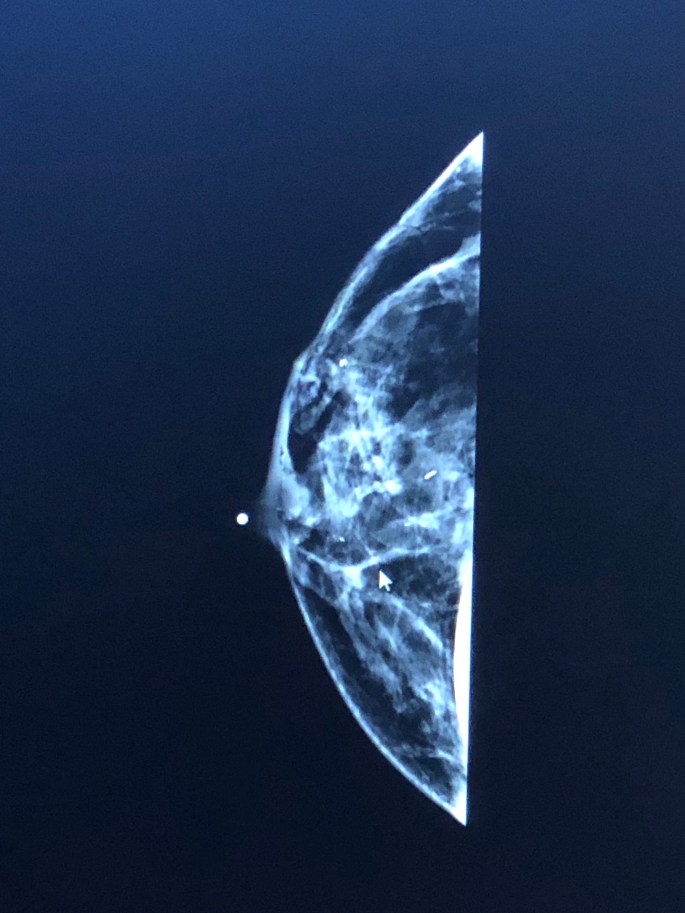

Well…YES, That is an ACTUAL clinical image of my breast tissue. For some of you (Like me, approx 3 1/2 weeks ago)…it may look strange…but, if you are like me, I had NO idea what I was looking at. Others might be able to tell something??? Who knows??? What I can now tell you is what the affected breast looks like. Feel free anyone to make comments…they are more than welcomed.

So, I went in for my routine well woman check-up last year @ 40…and was told to go and have my mammogram. So, I did…and was called back after Mammo #1. WHAT!!! NO!!! (It is VERY noteworthy at this point to share that my grandmother (Mother’s Mother) died of brest cancer. It WAS post-menopausal. (That will, I think, come into play more later…especially since I am pre-menopausal. I had more mammogram images done…then called in for sonogram…and the radiologist calls me into his office and shares that, he has concerns wtih some suspicious calcifications, but given it was my first imaging (aka my “base line”) hee wanted to just make me aware and monitor.

It felt like I was in the sonogram FOREVER! It was more like 45 mins, but not so fun. Actually, not painful…juus stressful. As you can imagine…your mind is going a million miles a minute. Back to the VERY fun chick waiting room I go…while waiting for the radiologist looks at yet more images. (PS-BTW…wonder what the image count on my tatas is at this point???????). This time I get called back again…but, now for a sonogram with and to be performed by the radiologist, himself. After that 20 minute procedure…I was told that I would get out of the robe and gown and dress and they would be calling me into the radiologists office. I am called in…and he says to me, “Well, I don’t like what I’m seeing. The area we saw last year has grown significantly and there is a new place as well.” He was VERY diligent about showing me what he was seeing and said normally he would order a biopsy. But, (and as with most things with me) apparently the other new area was/is RIGHT behind the right nipple. So, he recommended a breast MRI. It was said that the MRI results would be up to 98%+ proof.